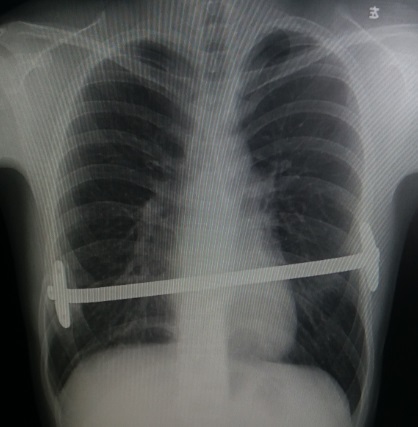

术前行X线检查:正位片提示胸壁内有钢板一条,钢板位置倾斜,脊柱轻度侧弯(图4)。侧位片提示前胸壁下部局部凹陷,钢板位置偏斜(图5)。行CT检查:可见胸壁内钢板影。横截面未见明显凹陷,但不同水平前后径明显不同(图6-10)。三维重建提示钢板影,前胸壁凹陷畸形(图11,12,13)。心电图及腹部超声检查未发现异常。

图4,X线检查:正位片提示钢板斜位,左侧高,右侧低,位置跨越两个肋间,脊柱轻度侧弯。